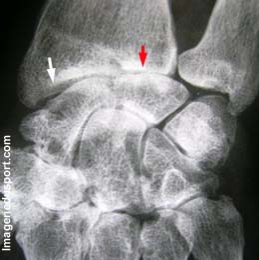

B - Radiographie du poignet de face : Pincement radio-carpien prédominant au niveau de l'espace radio-lunaire comparativement à l'espace radio-scaphoidien (flêche blanche). Aspect d'erosion au niveau de la surface articulaire distale du radius.

Polyarthrite rhumatoïde avec atteinte de la styloïde de l'ulna, de l'interligne radio-carpien et des MCP.